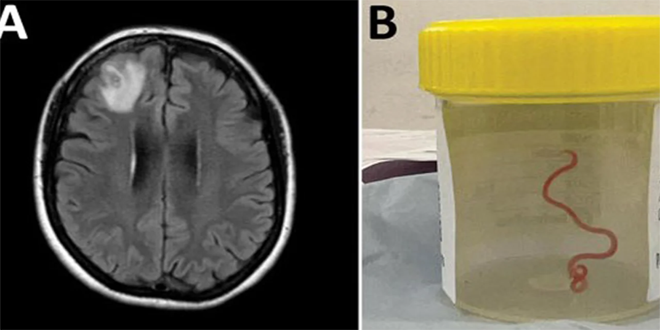

وحسب وكالة فرانس برس رصد الأطباء من خلال التصوير بالرنين المغناطيسي “آفة ذات شكل غير مألوف” في الجزء الأمامي من دماغ الأسترالية البالغة 64 عاماً والتي كانت تعاني فقدان الذاكرة وتبين أن هذه الآفة هي عبارة عن دودة من نوع “أوفيداسكاريس روبرتسي” الدائرية التي يبلغ طولها ثمانية سنتيمترات، وهي بحسب الباحثين طفيلية تعيش عادةً لدى حيوانات الكنغر والثعابين في أستراليا ولدى حيوانات في مناطق أخرى من العالم، ولكن لم يسبق رصد مثيل لها لدى البشر.

وقال اختصاصيّ الأمراض المعدية الدكتور سانجايا سيناناياكي إنها “أول حالة على الإطلاق في كل أنحاء العالم يرصد فيها وجود أوفيداسكاريس لدى إنسان… كما أنها أيضاً على حدّ علمنا، أول حالة تصيب دماغ أحد أنواع الثدييات، سواء أكان بشرياً أم غير ذلك”.